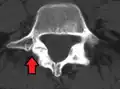

Anterolisthesis L5/S1. Blue arrow normal pars interarticularis. Red arrow is a break in pars interarticularis. -

Isthmic anterolisthesis is where there is a defect in the pars interarticularis (spondylolysis).[15] It is the most common form of spondylolisthesis; also called spondylolytic spondylolisthesis, it occurs with a reported prevalence of 5–7 percent in the US population. A slip or fracture of the intravertebral joint is usually acquired between the ages of 6 and 16 years, but remains unnoticed until adulthood. Roughly 90 percent of these isthmic slips are low-grade (less than 50 percent slip) and 10 percent are high-grade (greater than 50 percent slip).[13] It is divided into three subtypes:[16]

- A: pars fatigue fracture

- B: pars elongation due to multiple healed stress effects

- C: pars acute fracture